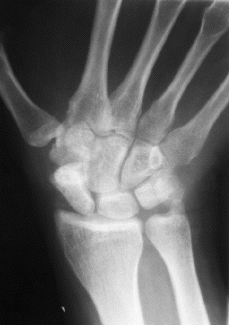

A pesar de todo hay pacientes que presentan una artrosis carpiana avanzada, e incluso algunos casos en los que existe una evidente ausencia de consolidación y, sin embargo, no presentan dolor en el postoperatorio tardío, lo cual hace pensar que son múltiples los factores que influyen para que una pseudoartrosis del carpo sea sintomática o no después de la actuación quirúrgica (Fig. 2) y que la estabilidad del carpo desempeña aquí un papel esencial.

A

BFigura 2. A y B: A los 15 años de evolución fracasada se objetivan cambios significativos radiológicos con persistencia de la pseudoartrosis, esclerosis importante y alteración en la morfología de este hueso. A pesar de ello, la movilidad y grado de función de su muñeca es bueno, con

una limitación moderada de la flexoextensión y en ausencia de dolor.